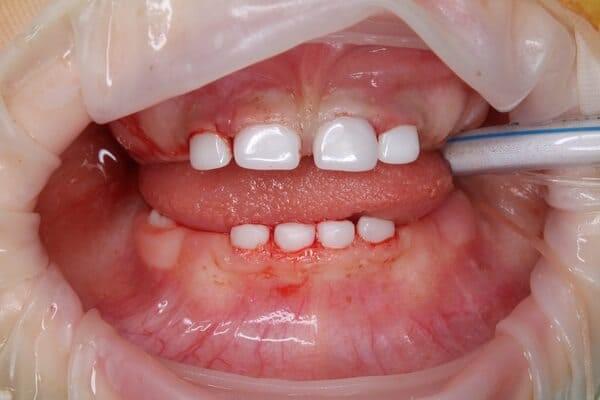

Пацієнт 2 років, уражено десять зубів, шість із яких потребують покриття коронками. В зв’язку зі значним об’ємом та складністю лікування прийнято рішення про лікування в умовах анестезіологічного забезпечення. Раніше була спроба пролікувати ці зуби застарілими методами, які не тільки не є ефективними відносно лікування, а ще і додають дитині комплексів через характерне фарбування зубів. Через високи естетичні вимоги дитини і батьків було прийнято рішення покривати естетичними цирконієвими коронками, як передні так і бічні зуби. Через 2,5 години дитина без інфекції в порожнині рота, з відновленим здоров’ям та естетикою посмішки може кусати, жувати, посміхатись без болю та дискомфорту. Останнє фото через 2 роки після лікування, оскільки естетичні коронки в дитячій стоматології - це надійність, естетика та функція.